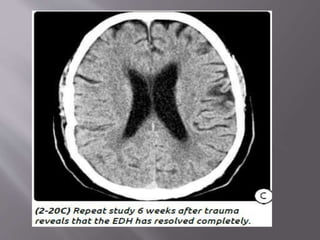

1) Epidural hematoma- two types : arterial EDH and

venous EDH. EDH r uncommon but r potentially

lethal. 90% EDH r arterial , 10% r venous. Venous

EDH r sec. to a fracture that crosses dural venous

sinus (transverse/sig , SSS)

 Imaging- Look for other comorbid lesions such

as "contre-coup" injuries, tSAH, and secondary

brain herniations, all of which are common

findings in patients with EDHs.

 CT - classic (arterial) EDHs is a hyperdense (60-

90 HU) biconvex extraaxial collection (2-18).

Presence of a hypodense component ("swirl"

sign) is seen in about one-third of cases and

indicates active, rapid bleeding with

unretracted clot.

“Buckling" the gray-white matter interface

inward.

Air in an EDH occurs in approximately 20% of

cases and is usually associated with a sinus or

mastoid fracture.